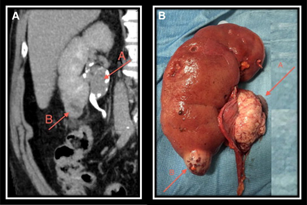

- Radical Nephrectomy – is the Ideal treatment for Kidney Cancer. These may require additional chemotherapy, immune therapy etc depending of extent of the disease or the recurrence of the cancer.

- Partial Nephrectomy – is the surgery for removal of entire tumour mass and preserving the healthy renal parenchyma.

Radical Nephrectomy is the standard surgery for any Renal Cell Carcinoma or Kidney Cancer.

Radical Nephrectomy consists of removal of entire kidney with its tumour in situ and without opening its covering (fascia) and is removed in to along with adrenal gland, surrounding fatty tissue and lymph nodes. These lymph nodes are the commonest site of spread of kidney cancers. Involvement of lymph nodes is considered as spread of tumour and increase its staging and reduces the outcome of surgery and may require other modes of therapy along with strict follow up and monitoring.

Partial Nephrectomy

Partial Nephrectomy sometimes can be the preferred treatment for many people with a early stage of kidney cancer. This can be done to remove a single localized tumor between 4 to 7 CMS. In this surgery only the cancerous tumor is removed leaving behind the healthy kidney tissue as much as possible. Hence, this surgery is performed either in a single kidney with the tumor or where it is of utmost importance to preserve the renal parenchyma. It is important to have the tumor free margins at the periphery